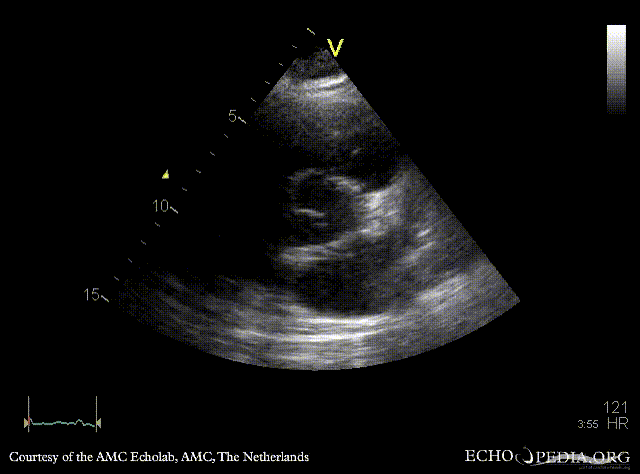

PLAX: no opening of aortic valve PLAX zoom